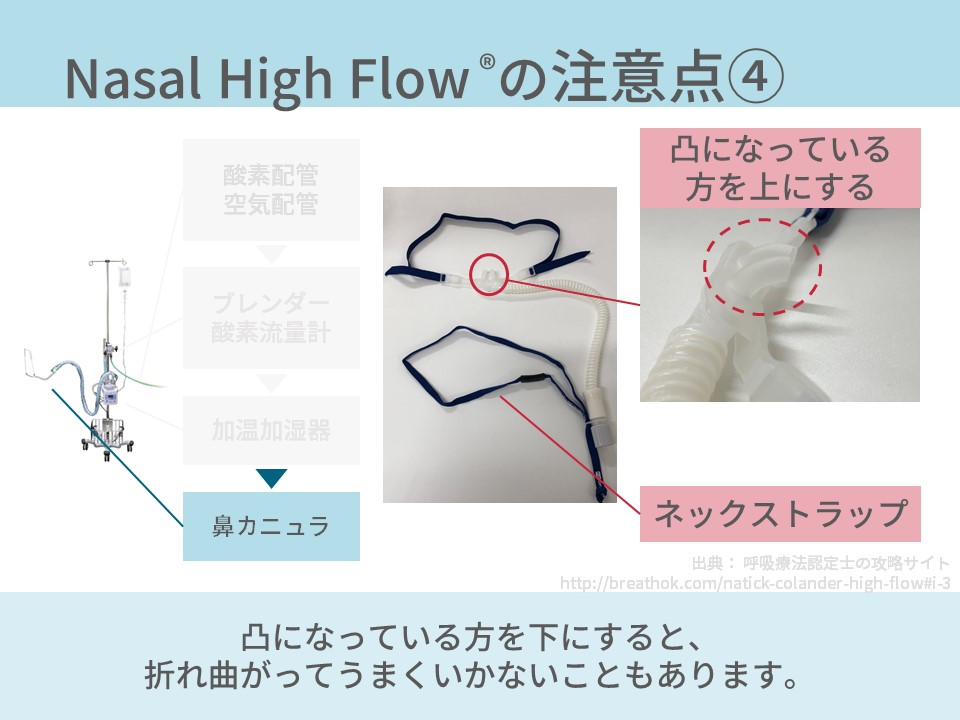

ネーザルハイフローの看護に必要な観察項目・設定の仕方を解説 一人でできるコキュトレ。

ネーザルハイフロー Nasal High Flow™ - 亀田メディカルセンター亀田総合病院 呼吸器内科 呼吸器道場。

今こそ知りたい! ハイフローセラピーのケアとアセスメント:急性期~終末期まで急性期 急性期ハイフローセラピーのアセスメントアイ・エム・アイ株式会社 IMI.Co.,Ltd。